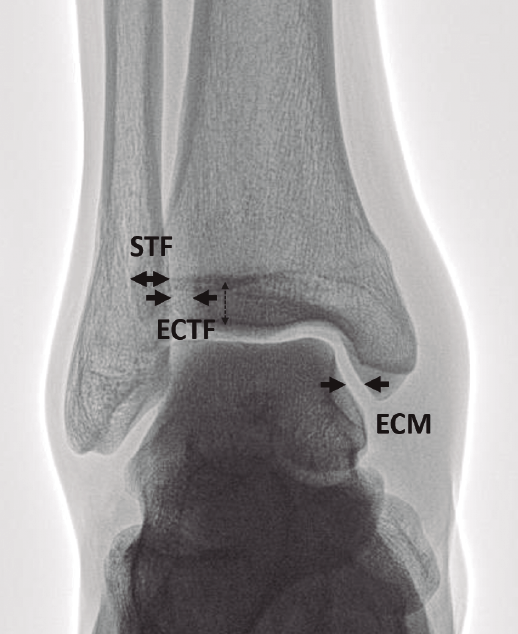

Figura 1. Parámetros radiográficos clásicos de sindesmosis estable en proyección anteroposterior (AP). ECM: espacio claro medial menor de 4 mm; ECTF: espacio claro tibiofifular menor de 6 mm; STF: solapamiento tibiofibular mayor de 6 mm.

En su artículo de 1989, Harper y Keller(11) establecieron los criterios radiográficos de una sindesmosis estable (Figura 1):

- Espacio claro tibiofibular (ECTF): distancia horizontal entre el borde lateral del maléolo posterior y el borde medial del peroné menor de 6 mm, tanto en la proyección AP como en la de mortaja.

- Solapamiento tibiofibular (STF): distancia entre el borde medial del peroné y el borde lateral del tubérculo tibial anterior mayor de 6 mm, un 42% del ancho del peroné en la proyección AP o mayor de 1 mm en la proyección de mortaja.

Las medidas son tomadas a 1 cm proximal del espacio articular del tobillo. - Espacio claro medial (ECM) ha sido otro parámetro habitualmente usado. Es la distancia entre el aspecto lateral del maléolo medial y el borde medial del astrágalo menor de 4 mm(12).